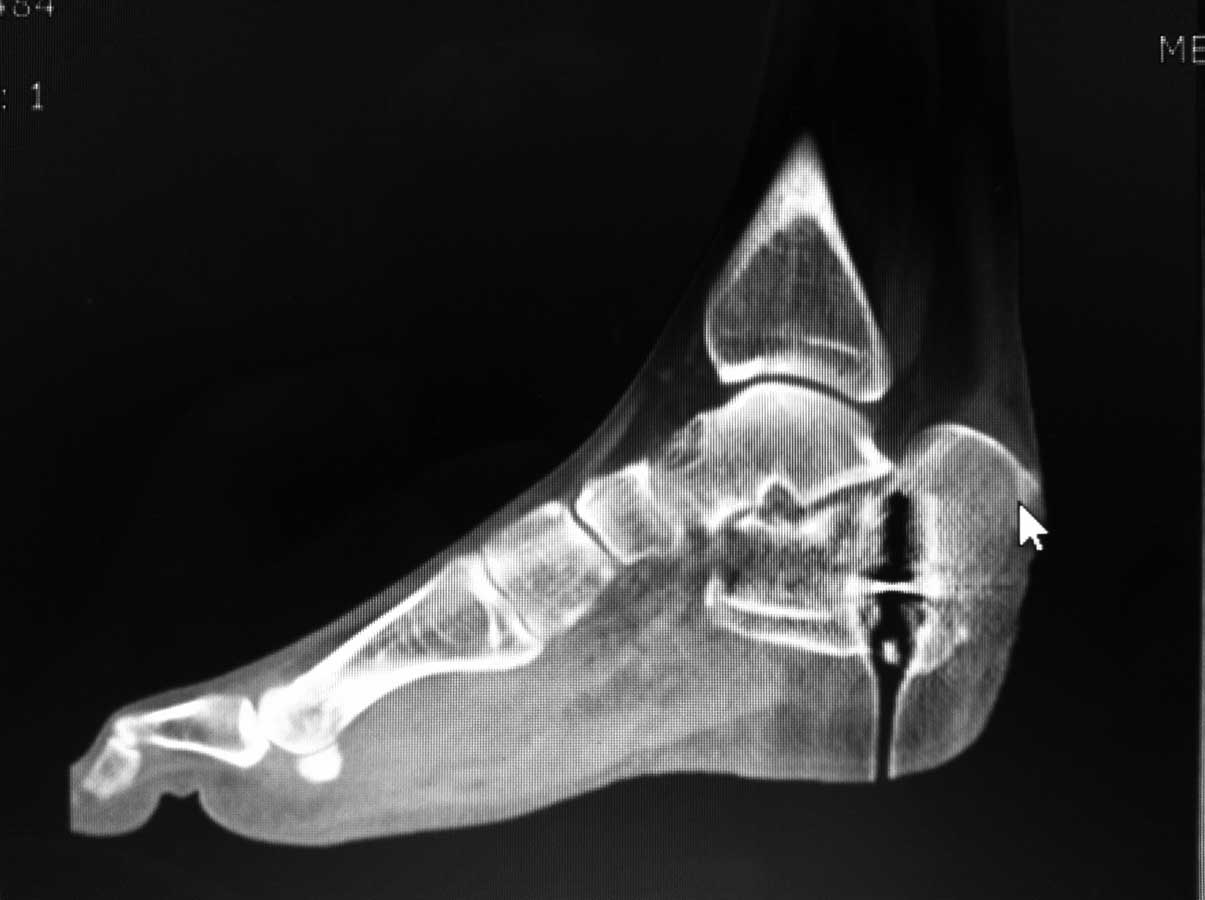

немного КТ

Используйте extensile латеральный L-доступ по Sangeorzan острым путем, до пяточного бугра. Используйте AO Y-пластину или реконструкционную. При ушивании идите от обоих углов к центру

Не все так страшно. Первым этапом нужно решить проблему с переломом шейки бедра. После установить скелетное вытяжение с точкой проведения спицы перед местом прикрепления ахиллова сухожилия. Этапно, грузами низвести основной фрагмент пяточной кости. В операционной в положении на животе воспользоваться методом Lopresty-Zhukov. При наличии ЭОПа операция длится 40-50 минут.